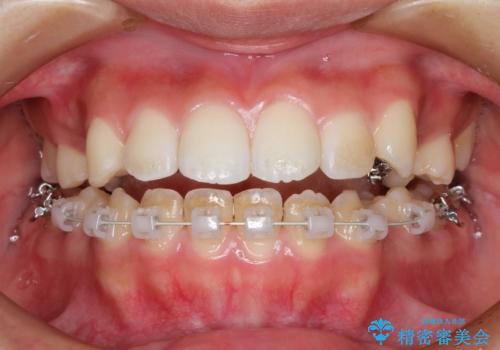

ハーフリンガル 半分裏側矯正による上下前突の抜歯矯正治療

- 矯正装置

- ハーフリンガル

- 治療期間

- 3年